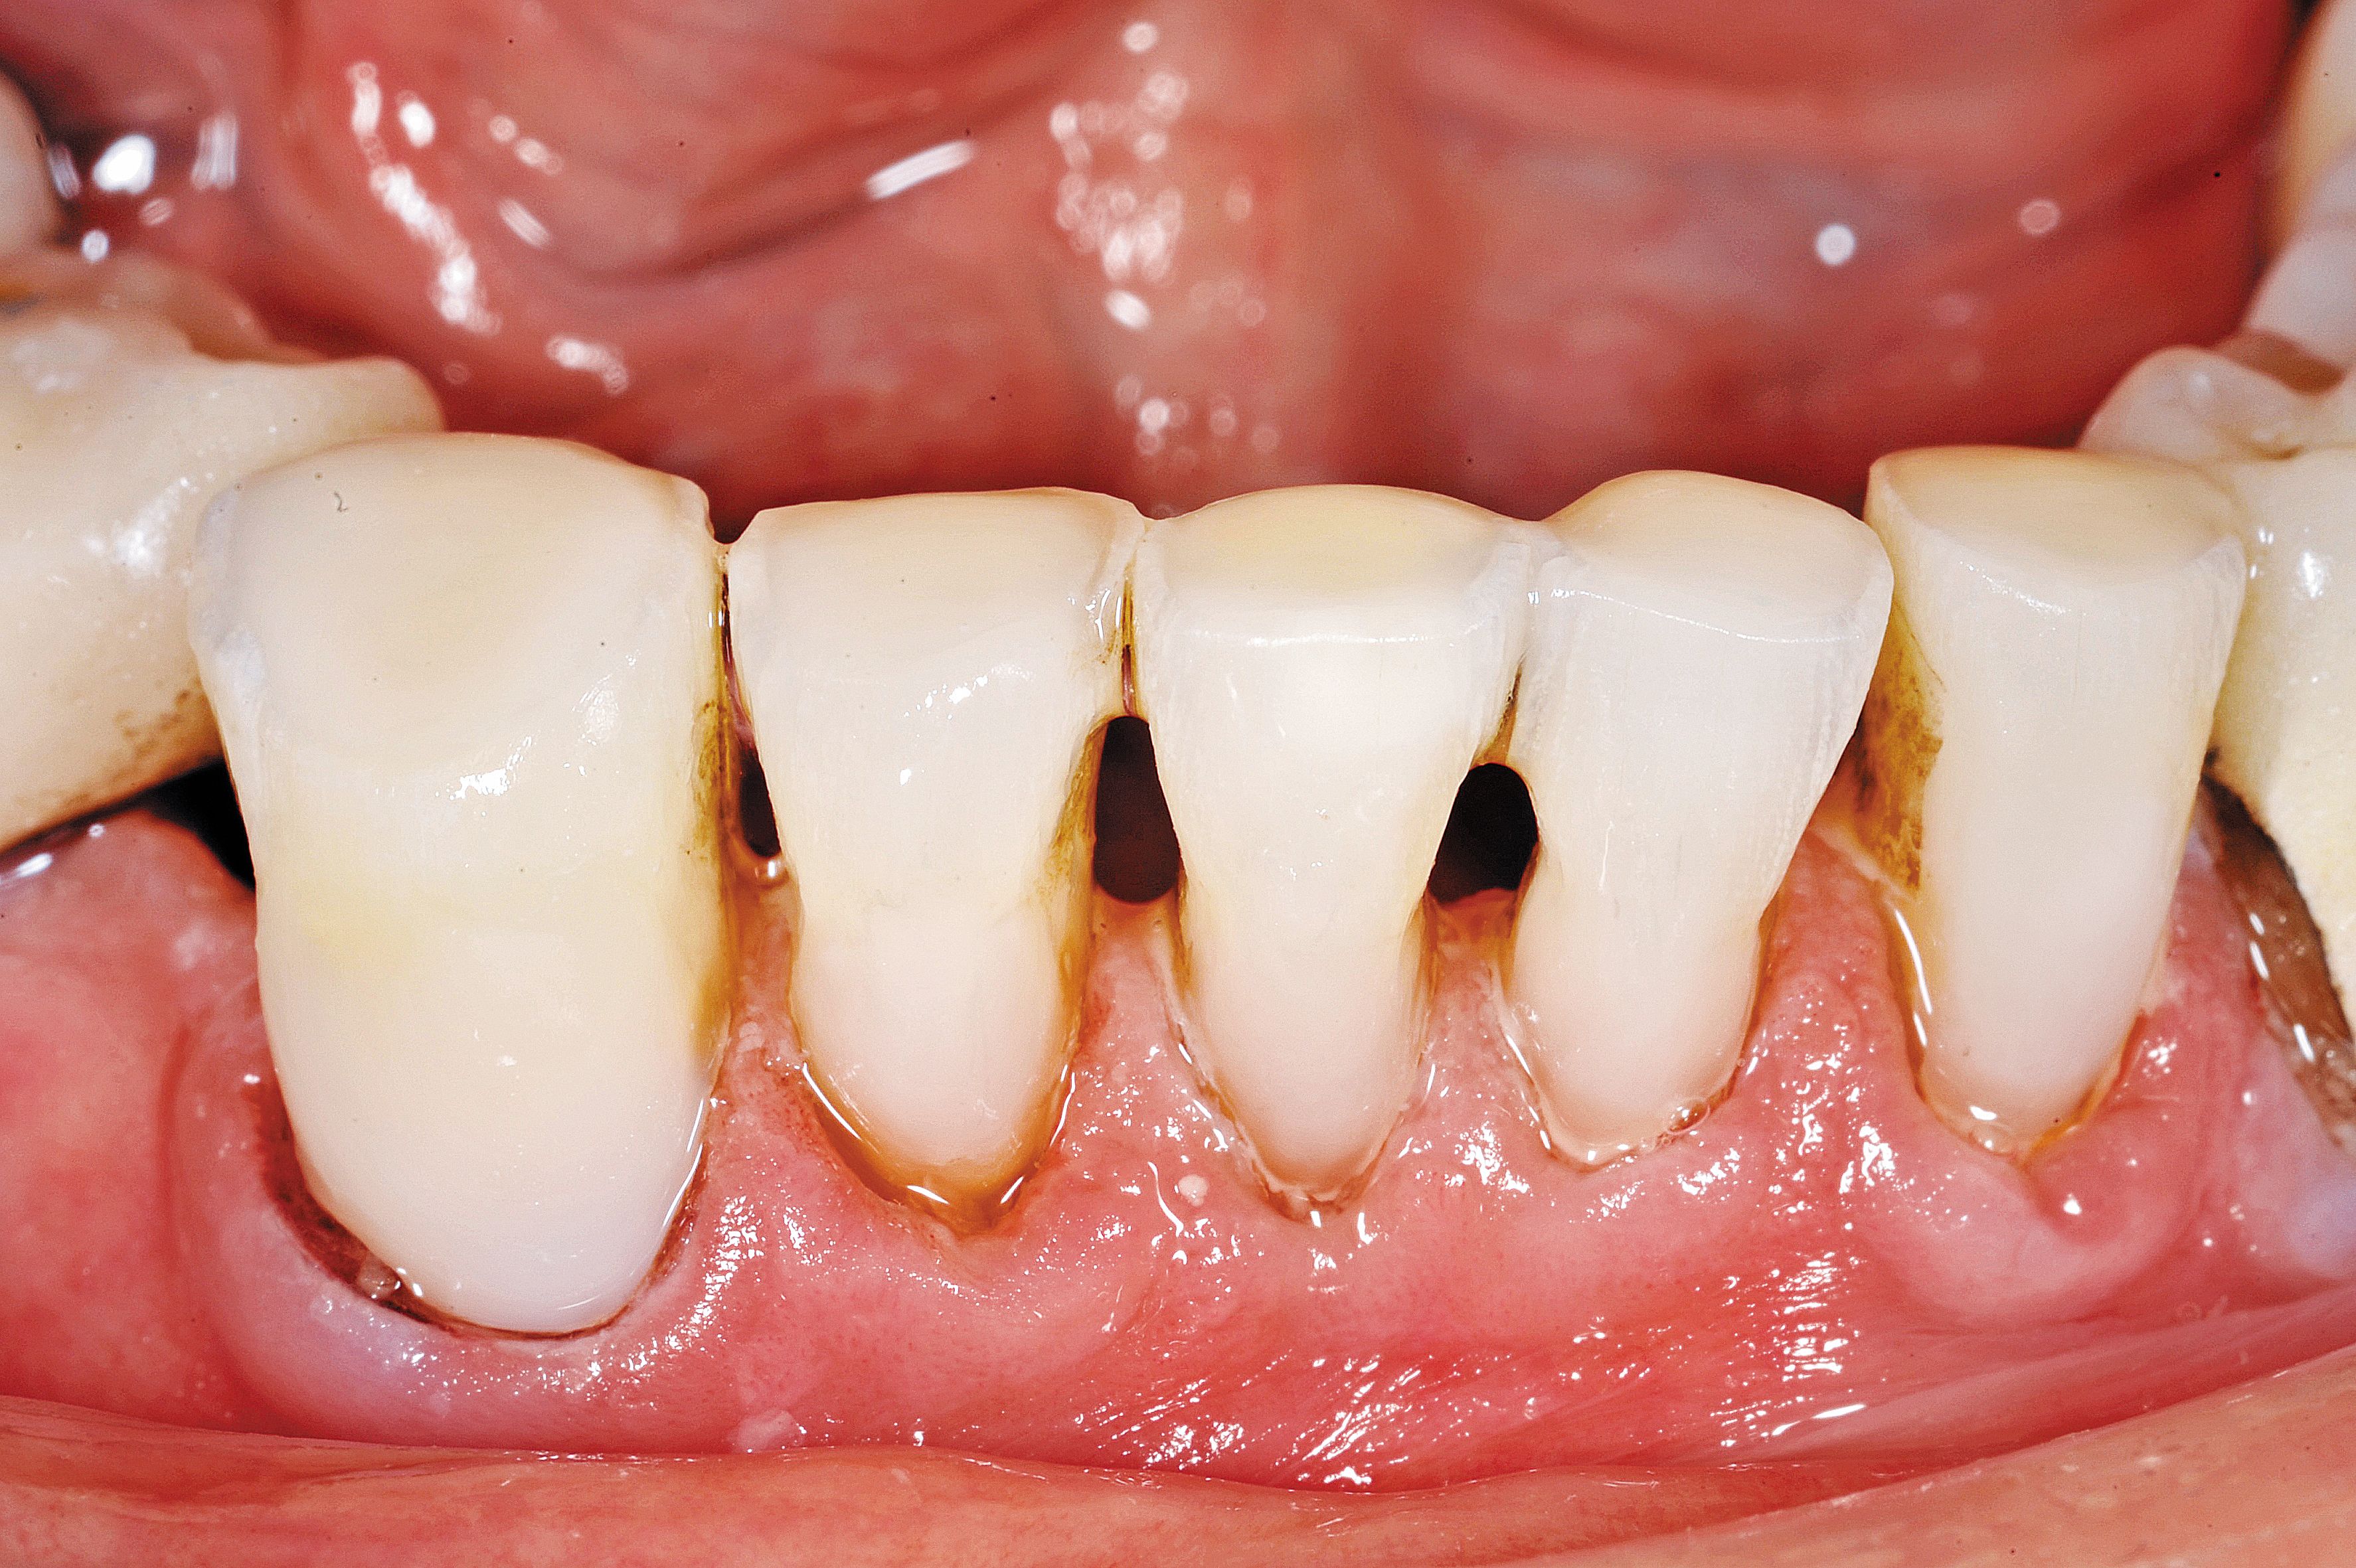

Fig. 2

The wear of the opposing denture and acrylic teeth was significant enough to see the secondary dentin of the pulp.